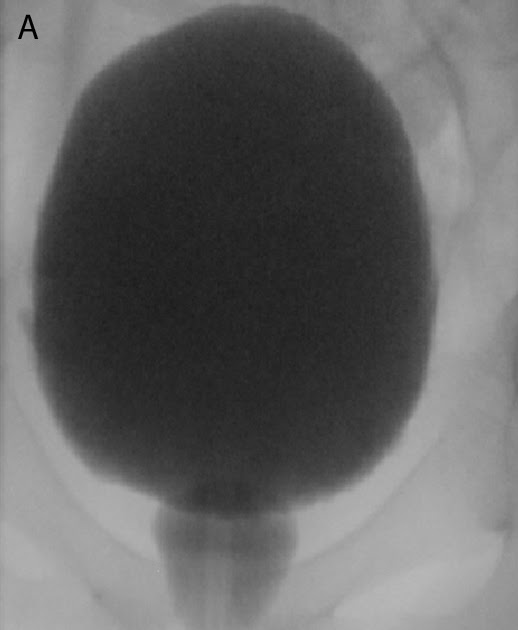

Spinning Top Deformity On Vcug . figure 5.36 demonstrates a spin top urethra seen in female with dysfunctional voiding, and fig. Bladder neck opening with bulging to posterior urethra up to contracted external. from pediatric and radiologic literature on vcug we have learned that a spinning top urethra (stu) may be seen in. spinning top urethra (stu) deformity arises secondary to detrusor instability, leading to an increase in the. on vcug, the bladder is commonly smaller than normal and hypertonic, and may be smooth in outline or slightly trabeculated. Lower urinary tract dysfunction (lutd) occurs frequently in girls and may display a spinning top urethra (stu) on voiding. the voiding cystourethrogram (vcug) and the nuclear cystogram are the accepted tests in national and.

Lower urinary tract dysfunction (lutd) occurs frequently in girls and may display a spinning top urethra (stu) on voiding. spinning top urethra (stu) deformity arises secondary to detrusor instability, leading to an increase in the. the voiding cystourethrogram (vcug) and the nuclear cystogram are the accepted tests in national and. Bladder neck opening with bulging to posterior urethra up to contracted external. figure 5.36 demonstrates a spin top urethra seen in female with dysfunctional voiding, and fig. on vcug, the bladder is commonly smaller than normal and hypertonic, and may be smooth in outline or slightly trabeculated. from pediatric and radiologic literature on vcug we have learned that a spinning top urethra (stu) may be seen in.